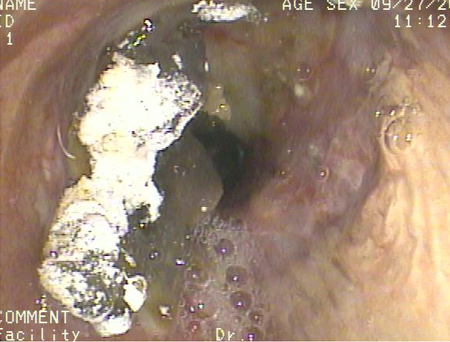

[25]Ansell G. Alimentary tract. In: Ansell G, Bettmann MA, Kaufman JA, et al, eds. Complications in diagnostic imaging and interventional radiology. 2nd ed. Oxford, UK: Blackwell Scientific; 1987:218-9.[Figure caption and citation for the preceding image starts]: Broncoscopia que muestra la aspiración de bario en el bronquio principal derecho de un paciente sometido a un trasplante de pulmón, tras un estudio con ingesta de solución de barioDe la colección del Dr. Kamran Mahmood [Citation ends].